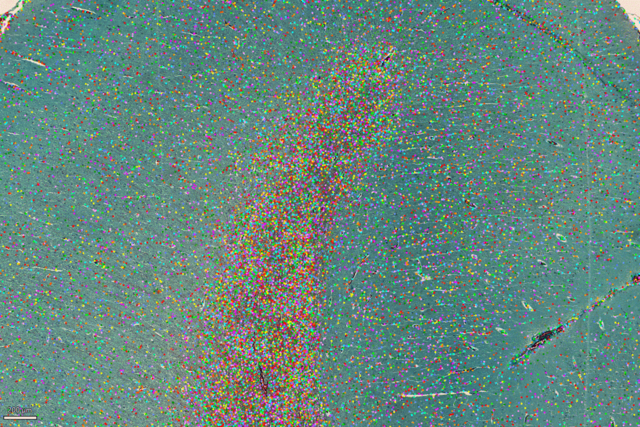

使用 LAS X Navigator进行拼图,然后使用 AIVIA 图像分析软件进行图像分割。